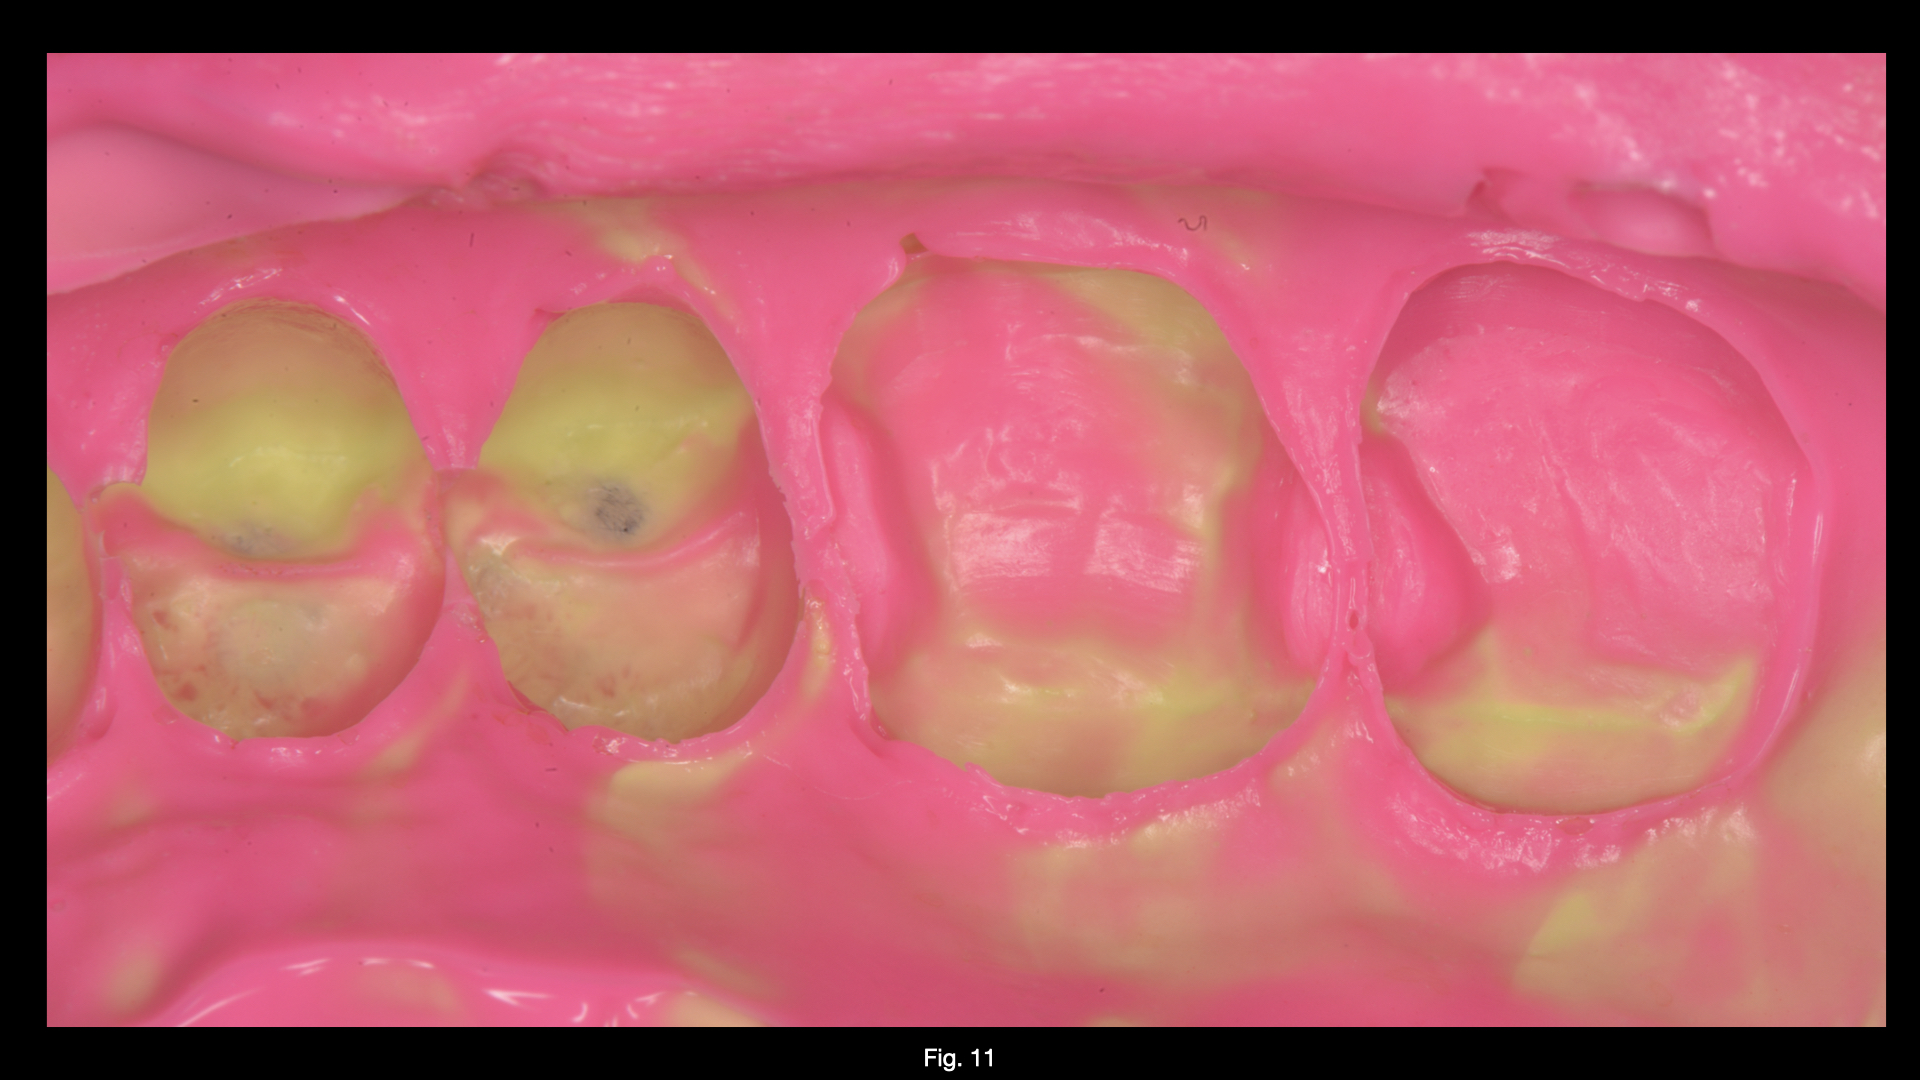

Figure 3

Figure 3. Teeth after caries removal Figure 4. Restoration of distal wall 1.4 (Garrison Composi-tight 3D Fusion System)